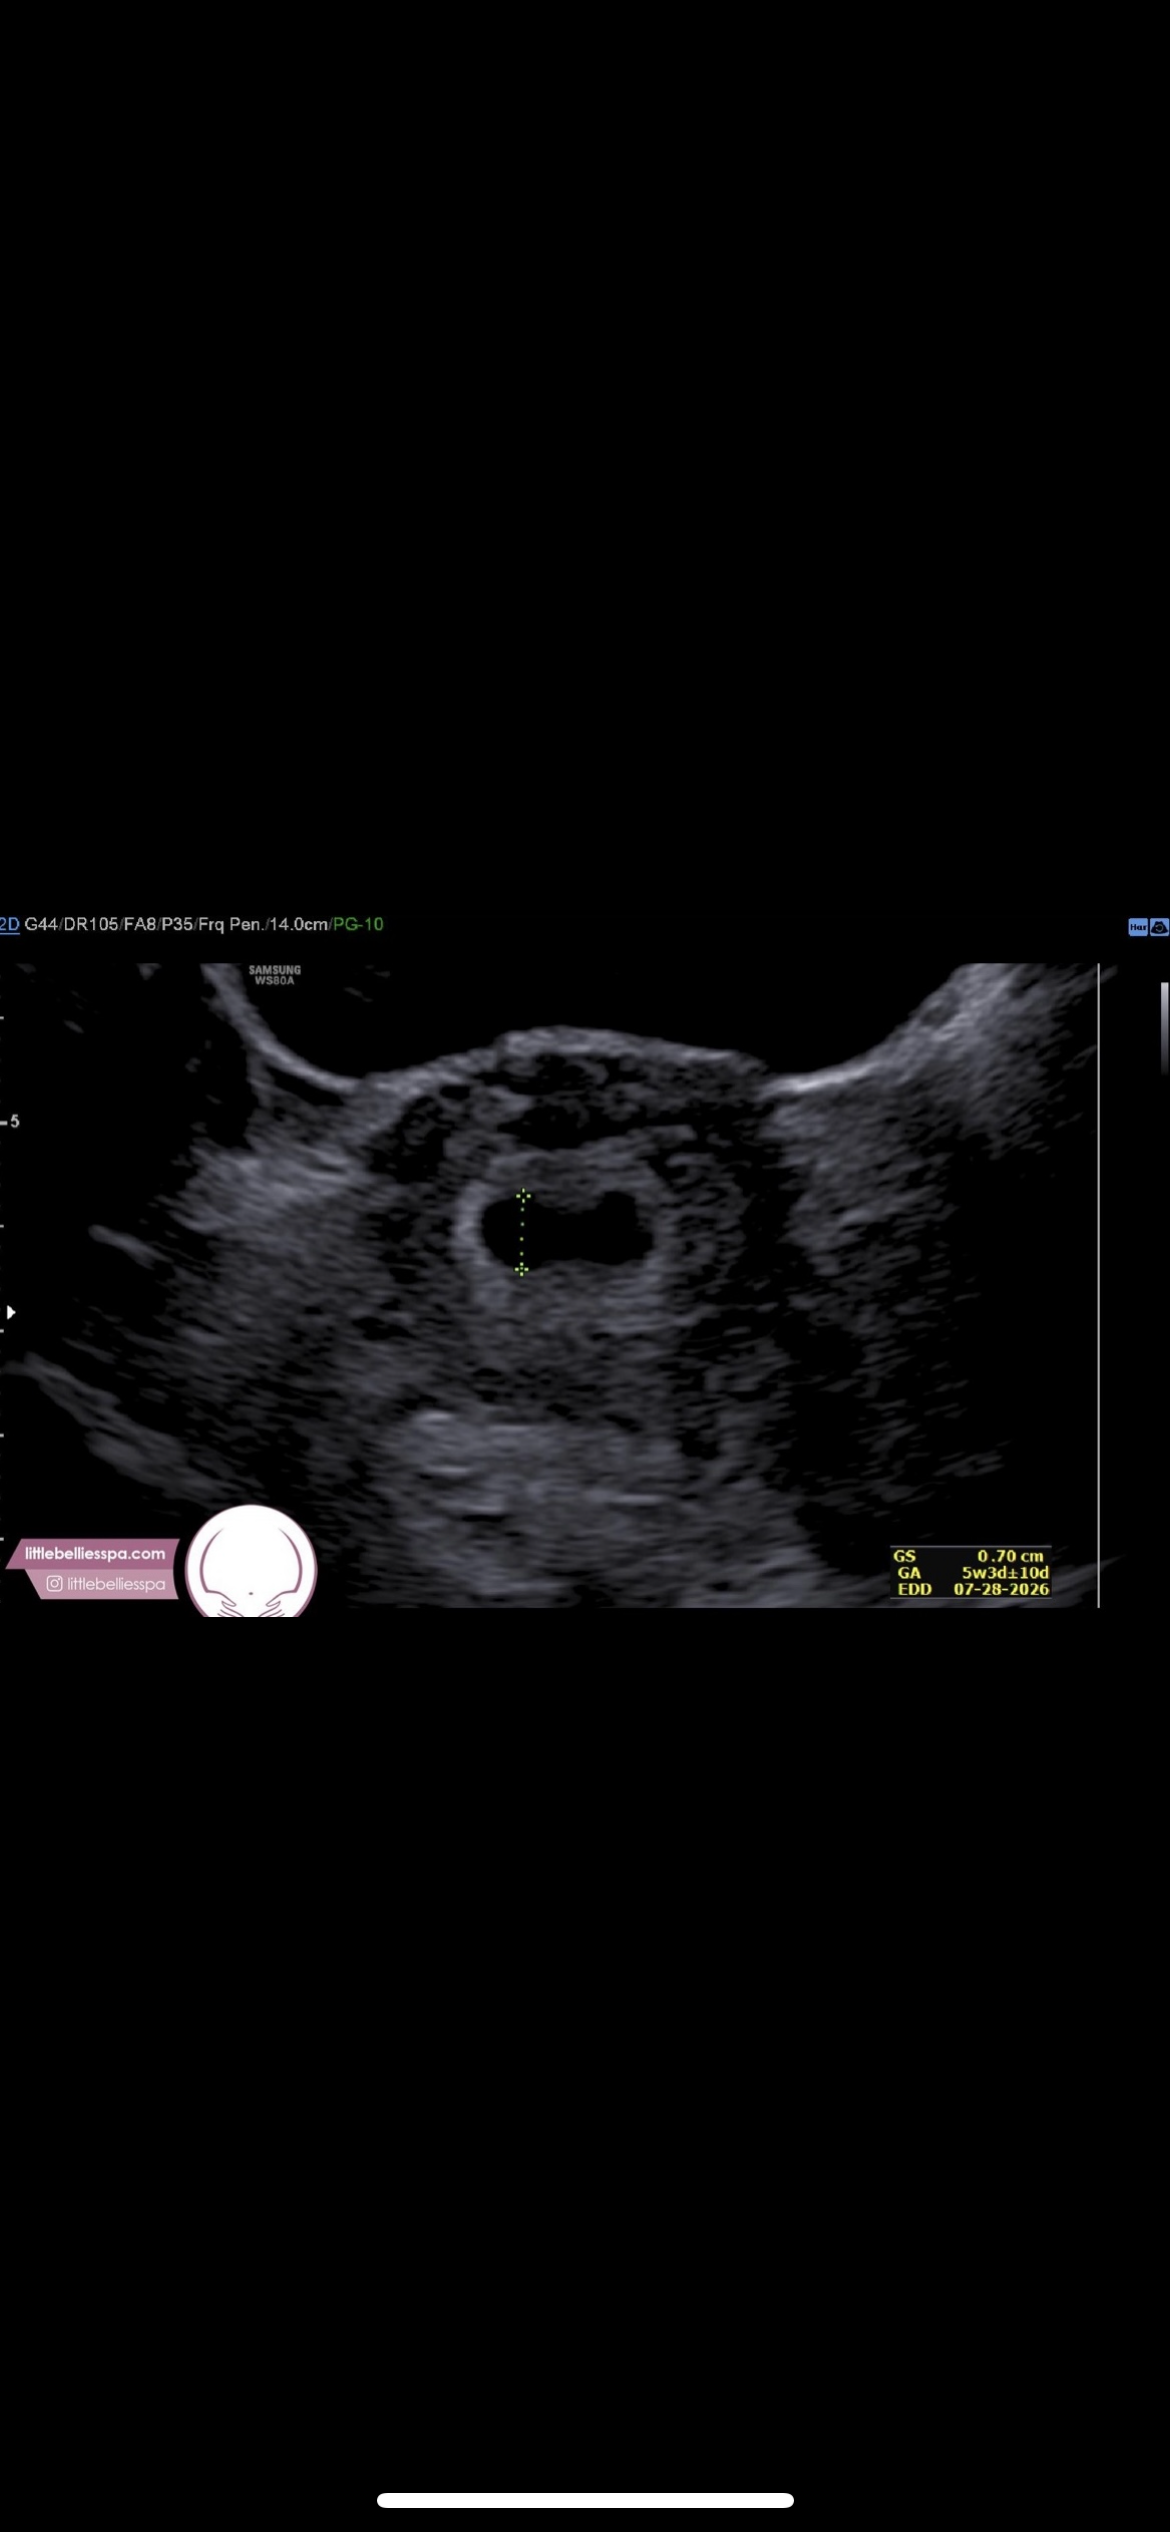

I did jump the gun on an ultrasound (not done through my regular doc office) and of course I knew just sac should be visible, but I am concerned at the shape or if it it’s too early to be worried about the sac shape because still so early.

But if someone could tel me if this looks normal, I would really appreciate it!!! Again, I know. Probably just paranoid.

• Your hCG rise looks strong and that is a good sign on its own. At around 5 weeks it is really common to only see a sac and for it to look a bit unclear or oddly shaped. Things change quickly from week to week, so an early scan is not great for judging much.